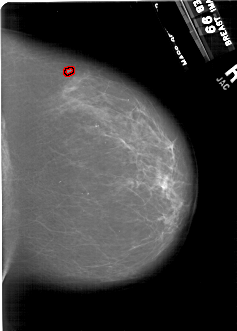

A_1848_1.RIGHT_CC

RIGHT_CC LINES 6271 PIXELS_PER_LINE 4486 BITS_PER_PIXEL 12 RESOLUTION 43.5 OVERLAY

FILE: A_1848_1.RIGHT_CC.OVERLAY

TOTAL_ABNORMALITIES 1

ABNORMALITY 1

LESION_TYPE MASS SHAPE IRREGULAR MARGINS ILL_DEFINED

ASSESSMENT 4

SUBTLETY 2

PATHOLOGY MALIGNANT

TOTAL_OUTLINES 1

BOUNDARY